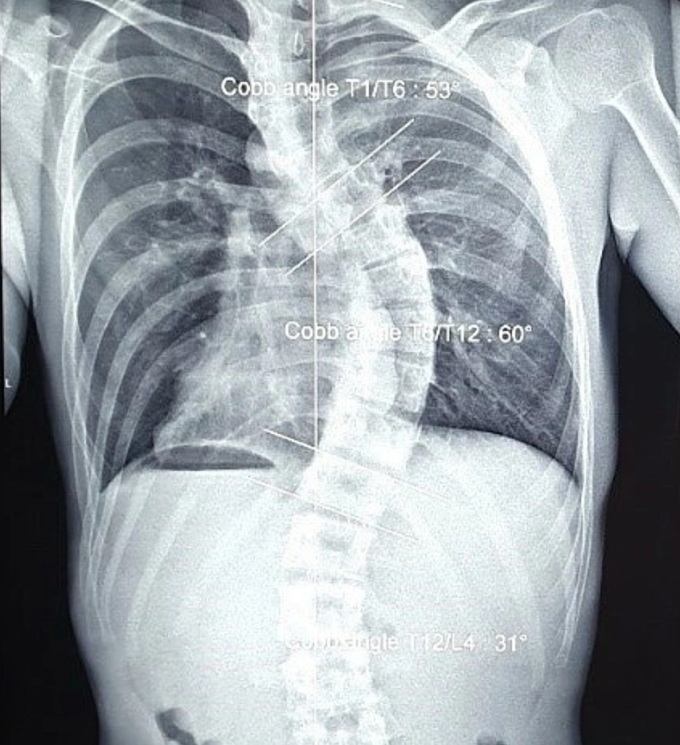

Thu, ở TP HCM, cũng chịu hậu quả tương tự. Bố mẹ phát hiện cô bị cong vẹo cột sống từ năm lớp 7 nhưng không đưa đi điều trị. Từ đó đến khi trưởng thành, Thu thường xuyên đau mỏi vùng lưng, khó thở, không thể leo nhiều tầng lầu. Sau 10 năm sống chung với bệnh, cô đi khám. Bác sĩ Calvin Q Trịnh, Giám đốc Đơn vị Phục hồi chức năng và hình thể HMR, chẩn đoán Thu bị vẹo cột sống ngực thắt lưng nặng, mất độ ưỡn sinh lý cột sống cổ, các đốt sống ngực đã biến dạng.